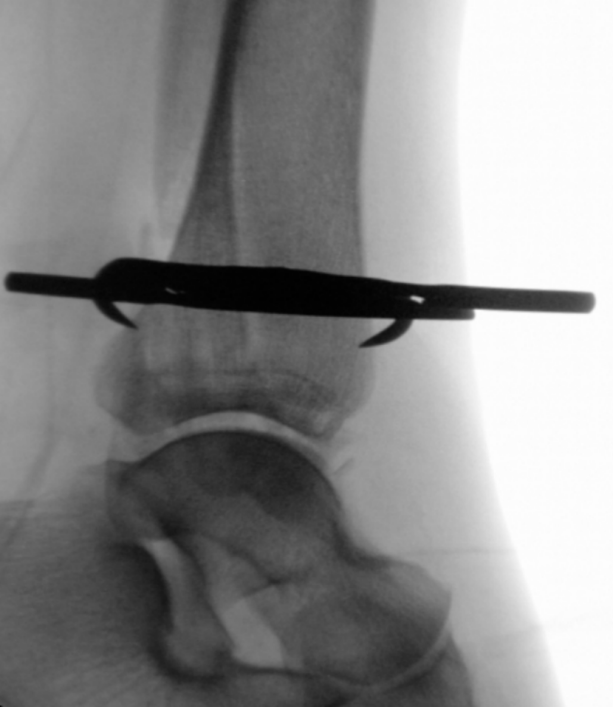

手术技术始于自腓骨尖向远端作短切口。锐性分离皮下组织,置入保护套筒。经套筒将导针置入髓腔并进入近端骨块。用空心开口器开髓,随后依次使用6.1毫米(远端)及3.1毫米、3.6毫米(近端)的钻头进行髓腔扩髓。扩髓过程在透视监控下进行,以避免皮质穿孔并确保钉道居中。将安装于瞄准器的腓骨髓内钉在透视引导下插入至预定深度,向外侧旋转,并用两枚前后向螺钉及两枚三皮质下胫腓联合螺钉锁定。未使用尾帽。最后于多平面进行透视记录(图5a–c)。彻底冲洗并止血后,将胫骨后肌腱复位,修复支持带,采用间断Donati缝合法分层闭合切口。敷以无菌敷料并用背侧夹板固定。

image.png

(a)

(b)

(c)

图 5. (a–c):最终术中透视图像:(a) 前后位视图,(b) 侧位视图,(c) 踝穴位视图。